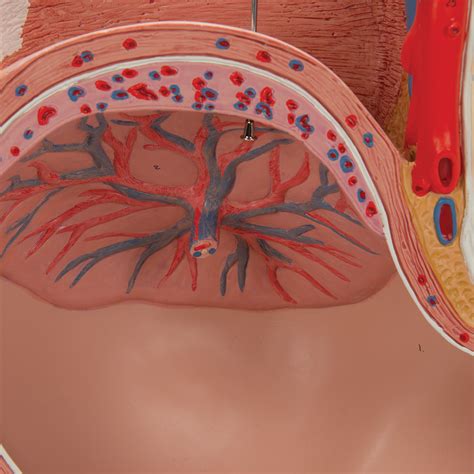

Na samom začiatku tehotenstva, ktoré sa počíta od prvého dňa poslednej menštruácie, dochádza k ovulácii a následnému oplodneniu vajíčka spermiou. Oplodnené vajíčko putuje do maternice a uhniezdi sa na jej výstelke. Z neho sa začínajú vyvíjať placenta, pupočná šnúra a plodové obaly. V tomto štádiu sa embryo podobá na žubrienku a jeho srdiečko sa začína deliť na predsiene a komory. Hoci embryo meria len niekoľko milimetrov, už sa mu vyvíjajú základné orgány ako obličky, pľúca a črevá.